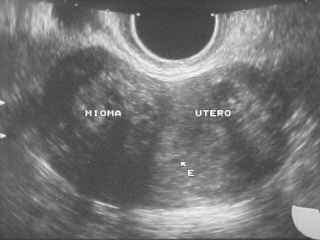

El mioma uterino es el tumor benigno más frecuente en mujeres, está presente, con o sin síntomas, en una de cada tres mujeres. Se desarrolla dentro o pegado a la pared del útero. Consiste en la proliferación anormal de células musculares del útero (mioma), a veces acompañada de proliferación de fibras del tejido conectivo del útero (fibroma).

El mioma uterino es una masa de tamaño variable, desde 1-2 centímetros de diámetro hasta varios kilos de peso, redondeada y de consistencia firme elástica, que aparece dentro del útero. Puede ser único o múltiple. Crece, en parte, por acción de los estrógenos, u hormonas sexuales femeninas, y puede llegar a alcanzar un tamaño enorme.

Mioma Uterino